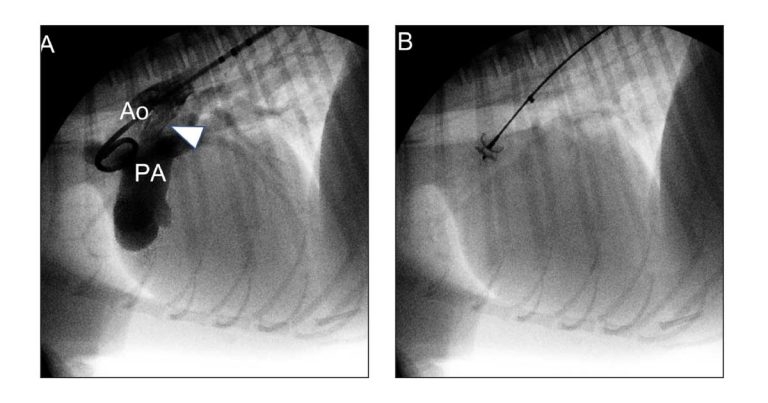

The BVP procedure for PS involves catheterisation of the right ventricle, through either a femoral or jugular venous approach, where contrast medium is injected to obtain a right ventriculogram and opacification of the main pulmonary artery (MPA) to visualise the stenotic valve.

A catheter is then advanced into the MPA and a soft guidewire is inserted inside the catheter until reaching a distal arterial branch. The catheter is then advanced over the wire to reach the same peripheral position and the soft guidewire is exchanged with a stiffer guidewire.

The catheter is subsequently retracted, leaving only the stiff guidewire in position. This will provide a steady support for the balloon catheter, which is advanced over the wire until the middle part of the balloon, marked by two radiopaque dots, is positioned at the level of the stenotic lesion.

At this point, the balloon is inflated either manually with a syringe prefilled with diluted contrast medium or via a dedicated inflation device with a manometer to avoid overinflation and the risk of balloon rupture.

During inflation, a central waist is observed as the balloon engages the stenotic valve and, continuing inflation, the waist disappears, and the balloon takes its proper inflated shape as the valve fusion is resolved. Right ventricular pressure can be measured before and after inflation to quantify the amount of pressure gradient reduction obtained following BVP (Figure 3).